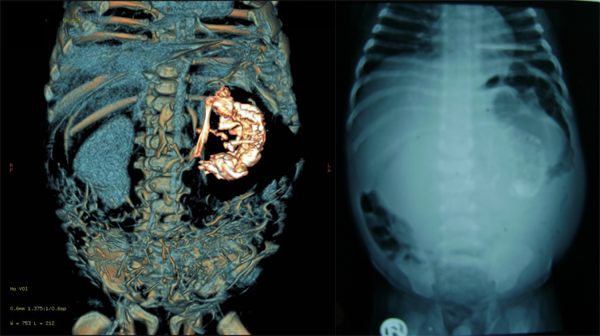

印度一名2岁1个月的幼儿(男),体内存在内寄生胎,此为其腹部CT及X光检查结果。左图:64层螺旋CT扫描出寄生胎的骨骼(右部白色部分)。右图:腹平片,左腹有纵向钙化带。图片来自:http://www.ncbi.nlm.nih.gov/pmc/articles/PMC2852393/。